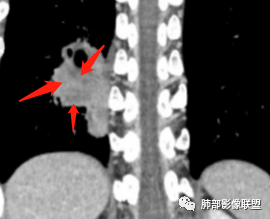

甄德强老师分析

多发小灶性坏死。强化程度轻,几乎观察不到完整血管影。

浅分叶,边界清

近端支气管堵塞

肺气肿背景

综上考虑鳞癌,鉴别低分化腺癌